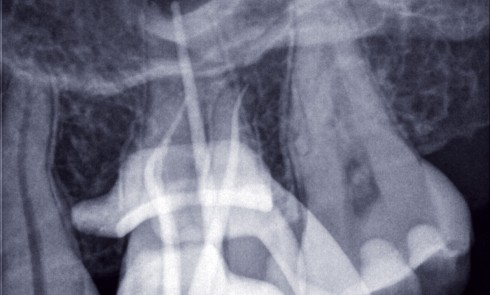

Les parodontites touchent environ 50 % de la population adulte (1) et provoquent la perte des tissus de soutien des dents...